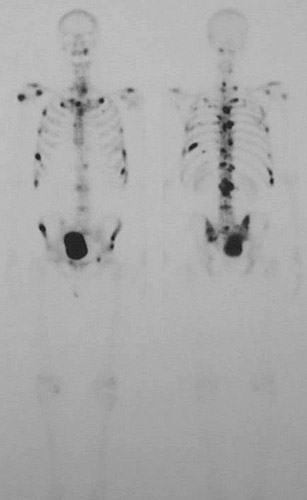

These two views from a nuclear medicine scan reveal numerous dark

"hot spots"

in a patient with a history of a lung carcinoma. The radioisotopic material is collecting in the

bladder

.